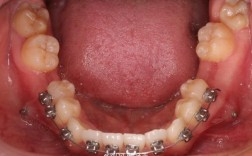

牙齿拥挤不拔牙矫正是可行的,但并非适用于所有情况,且需要严格的评估和特定的条件,其核心在于创造额外的空间来解决拥挤问题,而不是通过拔除牙齿来释放空间,以下是对牙齿拥挤不拔牙矫正的详细分析:📍一、不拔牙矫正的前提条件(关键!)不拔牙矫正能否...